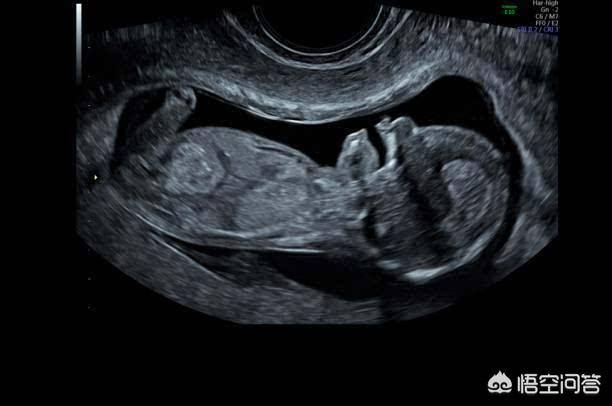

超音波検査では、胎児の位置が正常かどうか、羊水量が異常かどうか、胎児の臍帯が首に巻きついているかどうか、胎児の発育が遅れていないかどうか、胎盤が少ないかどうかなどを調べることができます。

妊娠中の超音波検査は、主に胎児の成長と発育、生理的活動、羊水の量、胎盤の状態を調べることができます。

超音波検査は、胎盤、胎児、羊水、臍帯の問題を発見するために使用され、妊娠全体に付随する妊婦健診の重要な部分です。

私たちの超音波検査ですべての問題を発見する方法はありません。多くの親は、陣痛や分娩の検査で定期的な検診を受けているのに、なぜ心房や心室の欠陥があるのだと言うでしょう。実際、このような単純な心臓病や、眼球が小さいなどの問題をすべて発見する方法はない。複雑な先天性心疾患や、脳の発達異常や無脳症などの奇形の多くは、超音波検査で発見することができ、奇形児の出産を避けるために適時分娩を誘発することができる。